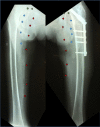

Peripheral arterial disease as seen on X-ray and arteriography